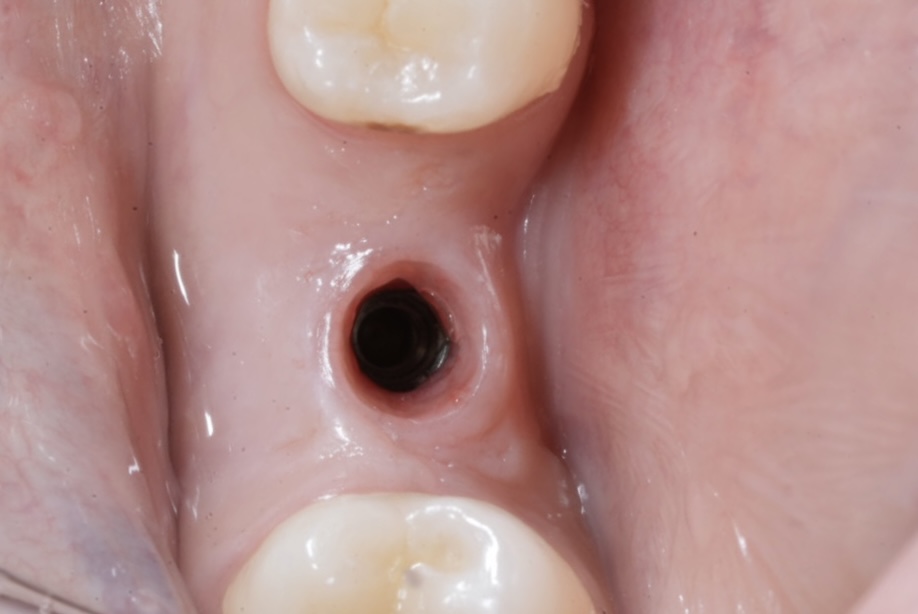

1. Soft-Tissue Maturation & Assessment

Clinical inspection revealed healthy peri-implant mucosa with an ideal emergence channel and a symmetrical gingival cuff. The tissue tone indicated stable integration of the Swiss implant platform.

1️⃣ Healed implant site showing emergence channel